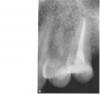

miha134 Опубликовано 28 июля, 2009 Поделиться Опубликовано 28 июля, 2009 Добрый день.У меня следующая проблема: зуб (четверка верхняя, снимок прилагается) стал реагировать на холодное, причем реакция идет не сразу, а через 2-3 секунды, с внешней стороны лица, если притронуться к щеке, тянущее ощущение зуба, боли нет. Подскажите, можно ли его лечить? или удаление? И вообще- что с ним? Ссылка на комментарий

Murenochka Опубликовано 28 июля, 2009 Поделиться Опубликовано 28 июля, 2009 Не могли бы вы уточнить - что все-таки с ним?Снимок,действительно,не очень качественный,но можно разглядеть на верхушке щёчного корня явления периодонтита.Это говорит о том.что необходимо срочно лечить зуб! Ссылка на комментарий